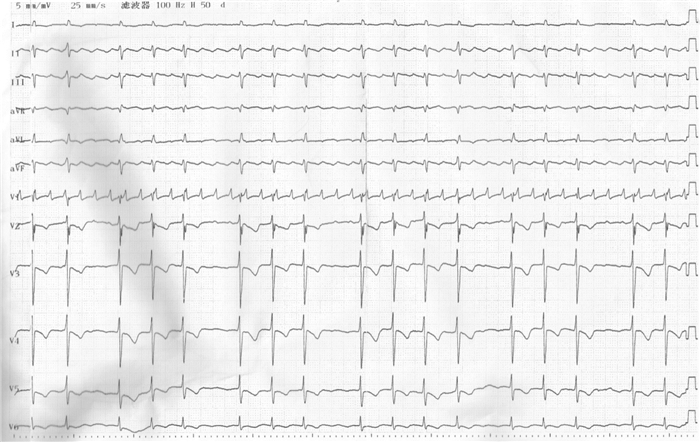

男,32岁,因间断胸闷、气短3年,加重2周入院。3年来患者因胸闷、气短多次就诊于外院,诊断为限制型心肌病。近2周上述症状加重,偶有端坐位呼吸及夜间阵发性呼吸困难,伴腹胀、食欲减退及少尿。既往吸烟史约20年,平均3-4支/d,已戒烟。否认高血压、糖尿病史、相关家族遗传病病史及寄生虫感染病史。入院查体:血压120/80 mmHg,端坐位,口唇发绀,颈静脉怒张,颈静脉搏动明显。双肺呼吸音粗,双下肺可闻及少量湿啰音。心界扩大,心率108次/min,律不齐,可闻及舒张晚期奔马律。肝肋下5 cm,双下肢中度凹陷性水肿。胸部CT示双心房增大,双肺散在炎症,双侧少量胸腔积液。心电图示(图 1)心房扑动,2:1-4:1传导,V1-V5导联T波倒置。肝、肾功能,血糖、心肌酶学、甲功八项未见异常。NT-pro BNP:6 110 pg/ mL(正常 < 100 pg/mL)。经胸心脏彩超示(图 2):左房(57.1 mm ×46 mm ×65.0 mm)、右房(47.3 mm×63.9 mm)增大;右室大小17.7 mm、左室大小32.7 mm;右室前壁厚度8 mm、室间隔17.7 mm、左室后壁13.3 mm;EF 62.4%;静息状态下左室壁收缩运动协调、运动幅度正常、心尖部收缩期近闭塞、左室流出道流速不快,E/A= 3.7,心内膜无明显增厚及回声增强,三尖瓣中度返流,二尖瓣轻度返流,心包少量积液。入院诊断为非梗阻性肥厚型心肌病舒张性心衰心律失常-心房扑动心功能Ⅳ级。经积极减轻心脏负荷、抗心律失常、抗感染、抗凝等对症治疗20 d,患者无明显呼吸困难,可平卧,双下肢无水肿。心脏MRI(图 3)结果示:双房增大,左、右心室壁及室间隔明显增厚、心室收缩功能正常,舒张功能受限;心脏灌注分析示心肌、心内膜未见延迟强化,支持上述诊断。出院后继续给予β受体阻滞剂、钙通道阻滞剂、抗凝及利尿治疗,随访中。

| 双心室大小正常,双房增大;射血分数正常;E/A3.7舒张功能严重受损 图 2 患者心脏彩超 |